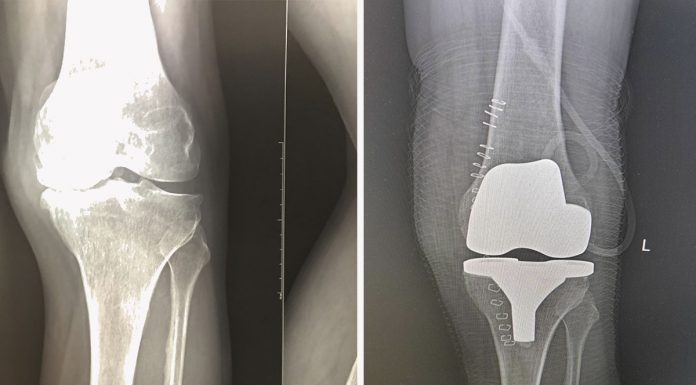

Где сделать эндопротезирование коленного сустава

Эндопротезирование коленного сустава – распространенная операция в травматологии, ортопедии и спортивной медицине. Установка импланта из прочных гипоаллергенных материалов решает ряд необратимых изменений, возникших при заболеваниях опорно-двигательного аппарата. Об услугах и клинике протезирования можно узнать, перейдя по ссылке https://medicalplaza.ua/content/endoprotezirovanie-kolennogo-sustava.

Протез коленного сустава помогает вернуться к активной жизни без боли и дискомфорта. Перед тем, как сделать операцию,...